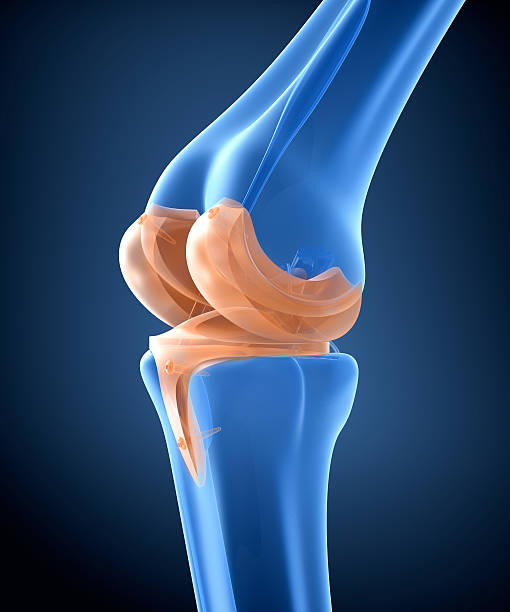

무릎 통증이 초기에 발견되고 적절한 치료를 받으면, 심각한 상태로 악화되는 것을 예방할 수 있습니다. 무릎 관절은 몸의 중심부에 위치하고 있어, 무게 중심의 일부를 지지하며, 매우 복잡한 기구로 구성되어 있습니다. 따라서 무릎 관절의 이상은 다양한 원인과 증상을 보일 수 있습니다. 초기에 발견하여 조치를 취하지 않으면, 무릎 관절은 더 큰 문제로 발전할 수 있어 이번 시간에는 무릎 통증 원인과 초기 치료에 대해 알아보겠습니다.

연골은 뼈와 뼈 사이의 마찰을 줄이고 충격을 흡수하는 기능을 합니다. 무릎의 연골손상은 무릎 통증의 일반적인 원인 중 하나입니다. 연골손상은 다양한 원인으로 발생할 수 있으며, 가장 흔한 원인은 무릎 관절 내의 충격이나 비대칭적인 압력에 의해 발생하는 외상입니다. 연골손상은 통증, 부종, 불안정성, 감각 손실 등의 증상을 일으킬 수 있습니다. 치료는 무릎 관절을 안정시키는 운동, 연골 재생을 촉진하는 약물 치료, 수술 등이 있습니다.